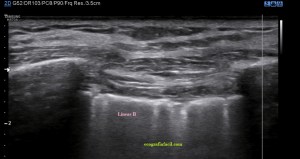

Si por el contrario, viésemos esta imagen…

2. Líneas B

Líneas B. Detalle.

Líneas B.Esta visualización del espacio intercostal indica Líneas B (flechas rosas), patología de diversa índole, normalmente, por la pérdida de la aireación normal en el contexto del síndrome intersticial y la presencia de tejido inflamatorio y/o líquido en esa región del pulmón que permite el paso de los trenes de ultrasonidos produciendo este tipo de imagen que es también otro artefacto, esta vez en cola de cometa.

Este artefacto aparece cuando el haz de ultrasonidos choca contra una interfase estrecha y muy ecogénica apareciendo detrás de esta interfase una serie de ecos lineales.

El aspecto de una línea B es lineal, perpendicular, hiperecogénica. Ojo, estas líneas pueden aparecer en «normalidad», pero cuando son únicas, cuando son 3 o más en un mismo espacio intercostal, deben saltarnos las alarmas, son una línea roja que debemos comunicar a la radióloga, para que eventualmente la paciente o el paciente se evaluado con otras técnicas.

En una zona donde hay Líneas B no puede haber Neumotórax.

Nota Importante: Las líneas A y B, además de aparecer en la pantalla tienen que cumplir una serie de requisitos para que sean consideradas como tales, como pueden ser en el caso de las líneas B, que aparezcan en un número por encima de 3 y que además esas líneas verticales lleguen hasta la profundidad de la pantalla.